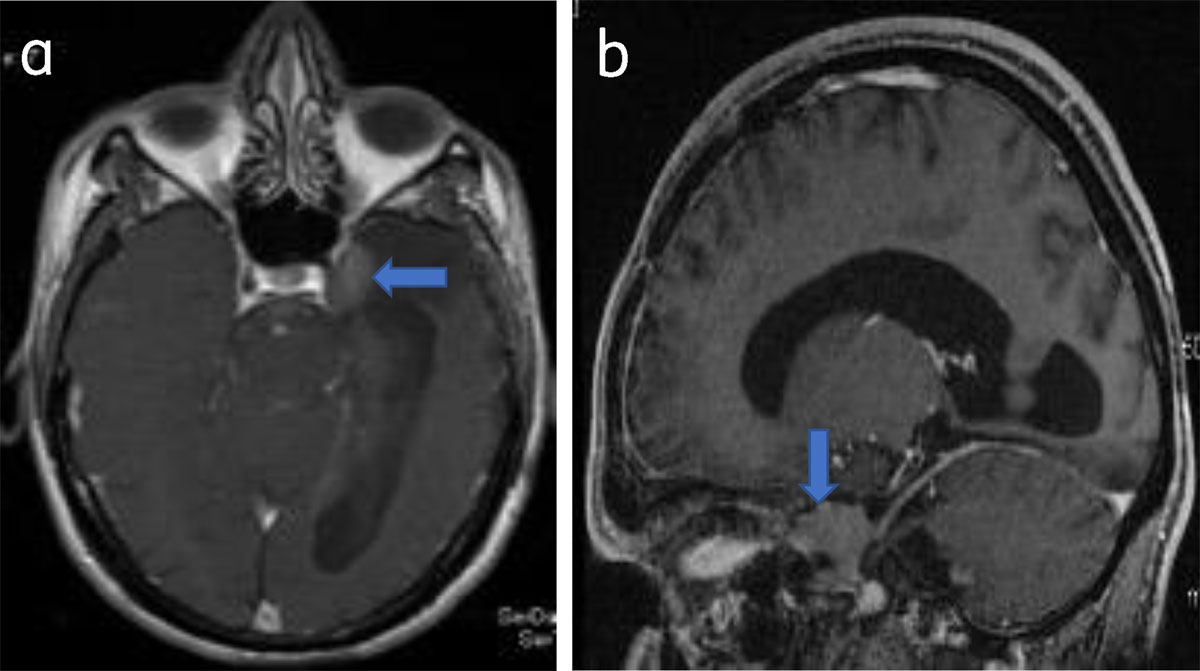

Figure 7

Parasellar meningioma: Axial (a) and sagittal (b) post-contrast T1W show a enhancing left parasellar meningioma (arrow).